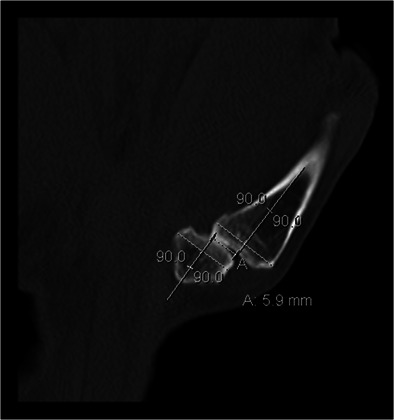

The subluxation was defined as the radial deviation of the long axis of the first metacarpal compared to the axis of the trapezium. The measurement (mm) was done on CT as follows: The coronal plan in which the TMC joint of the thumb was best depicted was selected. Two right angles were drawn to represent the axes of the bones, and the distance (a) between the axes was measured in level of the joint (Fig. 1). The reliability of the measurements of the subluxation was measured using all scans (172 hands), and we found the correlation between measurements 1 and 2 good with a correlation coefficient of 0.66.

Fig. 1.

The subluxation (a) measured as the radial deviation of the long axis of the first metacarp compared to the axis of the trapezium